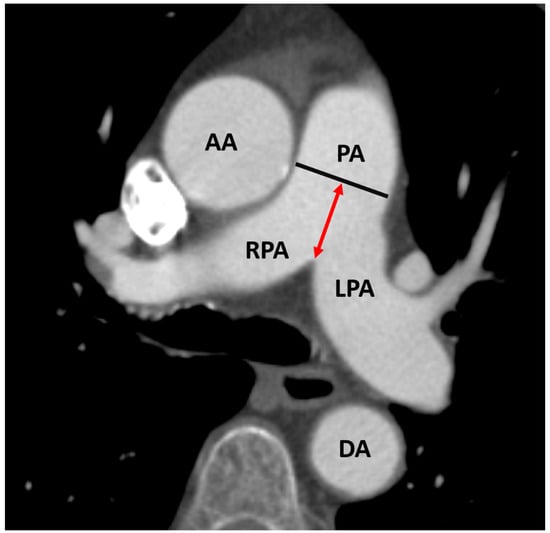

2.3. CTA Protocol and Measurement of PA Diameter for PH Assessment

- Sudo, M.; Sugiura, A.; Treiling, L.; Al-Kassou, B.; Shamekhi, J.; Kütting, D.; Wilde, N.; Weber, M.; Zimmer, S.; Nickenig, G.; et al. Baseline PA/BSA ratio in patients undergoing transcatheter aortic valve replacement–A novel CT-based marker for the prediction of pulmonary hypertension and outcome. Int. J. Cardiol. 2021, 348, 26–32. [Google Scholar] [CrossRef] [PubMed]

- Eberhard, M.; Mastalerz, M.; Pavicevic, J.; Frauenfelder, T.; Nietlispach, F.; Maisano, F.; Tanner, F.C.; Nguyen-Kim, T. Value of CT signs and measurements as a predictor of pulmonary hypertension and mortality in symptomatic se-vere aortic valve stenosis. The international journal of cardiovascular imaging. Int. J. Cardiovasc. Imag. 2017, 33, 1637–1651. [Google Scholar] [CrossRef] [PubMed]